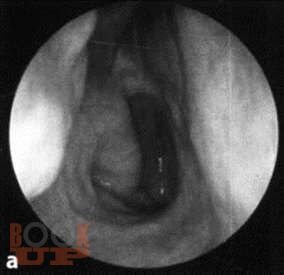

Методические рекомендации позволяют студентам, проходящим цикл практических занятий по оториноларингологии, помочь в освоении практических навыков.

Описаны подробные методики исследования носа, околоносовых пазух, глотки, гортани и уха, а также основные диагностические и лечебные манипуляции.